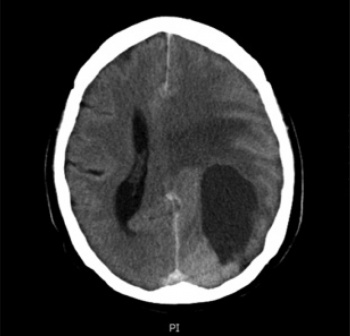

Investigations for the neurological symptoms included CT scan pre-contrast and post-contrast, which revealed a 6cm x 3cm complex mass lesion, in the left parietal-occipital area in the brain parenchyma with mass effect (see Figure 1).

Figure 1: CT brain scan showing 6cm x 3cm mass lesion (partially cystic) in the left parietal and occipital lobes